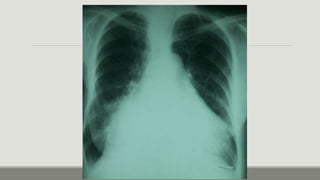

Rx de tórax

Fase

intersticial:

Pérdida de la definición de los vasos

pulmonares, engrosamiento de los

tabiques interlobulillares (líneas A y B de

Kerley), nódulos acinares perhiliares,

manguitos peribronquiales,

engrosamiento de las cisuras.

Rx de tórax Fase intersticial: Pérdidade la definición de los vasos pulmonares, engrosamiento de los tabiques interlobulillares (líneas A y B de Kerley), nódulos acinares perhiliares, manguitos peribronquiales, engrosamiento de las cisuras.